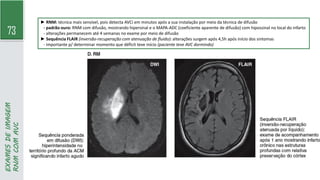

► RNM: técnica mais sensível, pois detecta AVCi em minutos após a sua instalação por meio da técnica de difusão

- padrão ouro: RNM com difusão, mostrando hipersinal e o MAPA-ADC (coeficiente aparente de difusão) com hipossinal no local do infarto

- alterações permanecem até 4 semanas no exame por meio de difusão

► Sequência FLAIR (inversão-recuperação com atenuação de fluido): alterações surgem após 4,5h após início dos sintomas

- importante p/ determinar momento que déficit teve início (paciente teve AVC dormindo)